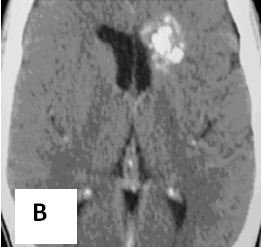

Hình 3. Hình ảnh di căn não đa ổ có lắng đọng canxi trên phim CT trước tiêm thuốc (A) và sau tiêm thuốc (B) của bệnh nhân ung thư dạ dày loại biểu mô tuyến chế nhầy có chảy máu trong u